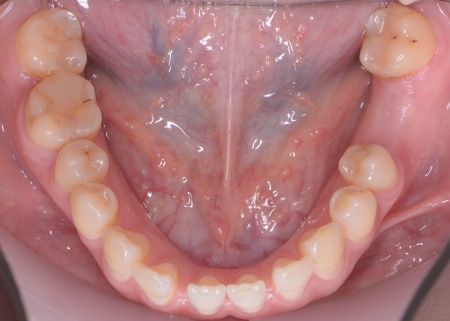

| カウンセリング | 拝見したところ、右上と左下の奥歯に強い痛みが出ていました。 レントゲンで確認した結果、どちらも歯の根が割れていることが判明しました。 歯の根が割れたまま放置すると噛むときの痛みが続くだけでなく、炎症が広がって周囲の歯や骨にまで影響を及ぼすおそれがあります。 また、上下の歯を噛み合わせた際に前歯が噛み合わず隙間ができる開咬(かいこう)と呼ばれる噛み合わせも見られました。 以上のことから、抜歯後に歯を補う治療と噛み合わせを改善するための治療が必要と診断しました。 |

患者様は「健康な歯をできるだけ守りたい」との理由から、③のインプラント治療を希望されました。 まず、右上と左下の奥歯を抜歯しました。 矯正がある程度進んだ段階で、右上と左下のインプラント手術を実施しました。 インプラント手術後は矯正治療の仕上げを行い、装置を外しています。 治療終了後、下前歯の間に見られる三角形のすき間(ブラックトライアングル)が気になるとのご相談がありました。 |